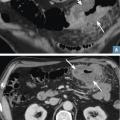

Un homme de 68 ans se plaint d’une altération de l’état général avec troubles du transit d’apparition récente et douleurs abdominales. Le scanner avec injection au temps portal montre un épaississement pariétal marqué du côlon transverse circonférentiel, bourgeonnant, avec contours irréguliers (fig. 3 ; flèches blanches). La graisse du méso est infiltrée au contact. On pose le diagnostic de cancer colique. La biopsie faite lors de la coloscopie le confirme : c’est un adénocarcinome.

Un homme de 68 ans se plaint d’une altération de l’état général avec troubles du transit d’apparition récente et douleurs abdominales. Le scanner avec injection au temps portal montre un épaississement pariétal marqué du côlon transverse circonférentiel, bourgeonnant, avec contours irréguliers (